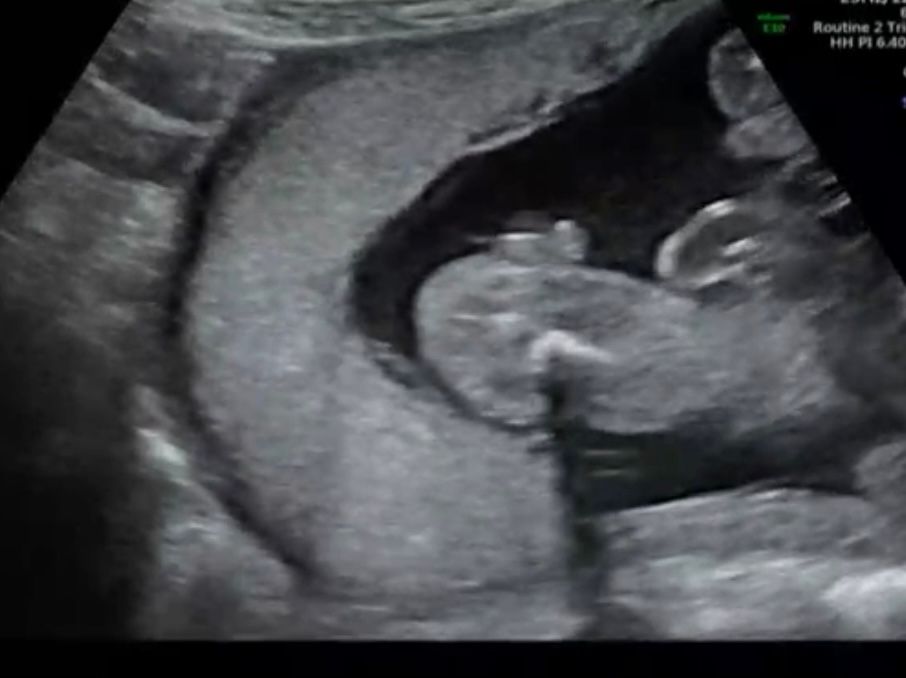

21 неделя Первая попытка определения пола Узи

Результаты УЗИДевочки, вот и настало мое время спрашивать знатоков, кто разбирается в узи писюнах😂

на 12-16 неделе никаких половых признаков вообще не было видно, поэтому я начала думать на девочку (Да и в предыдущем посте 99% людей нагадало мне девочку). А сегодня учись обрадовал тем, что на 90% уверен, что это мальчик! (Мы с мужем и хотели мальчика)

на узи все было неплохо видно, однако у мужа страх, что бубенцы испаряться. Вот хотелось бы вашего мнения

Как по мне, это точно мальчик. Но хотелось бы увидеть ваши снимки узи (если вы не против поделиться) в 19-24 недели, чтобы лучше понять и сравнить, да и мужа успокоить)

На 21 недели уже видно хорошо пол.Так что,думаю врач не ошибся,на Вашем снимке видно,что мальчик.Я ходила смотреть пол на 19 недели,врач хотела сделать снимок наших бубенчиков,но малыш упорно их прятал.В 21 неделю на 2 скрининге подтвердили мальчика.Так что,если это мальчишка,то бубенцы никуда не денутся уже)

Хорошие такие уже бубенчики с писюнчиком видны, сомневаюсь, что это пуповина😅

Валерия, нам Сказали, что мальчик, но подтвердить уже точно можно будет в 24 недели) До этого вообще пол не смотрели

наш писюн, на таком сроке все уже видно, пусть желание сбудется:)